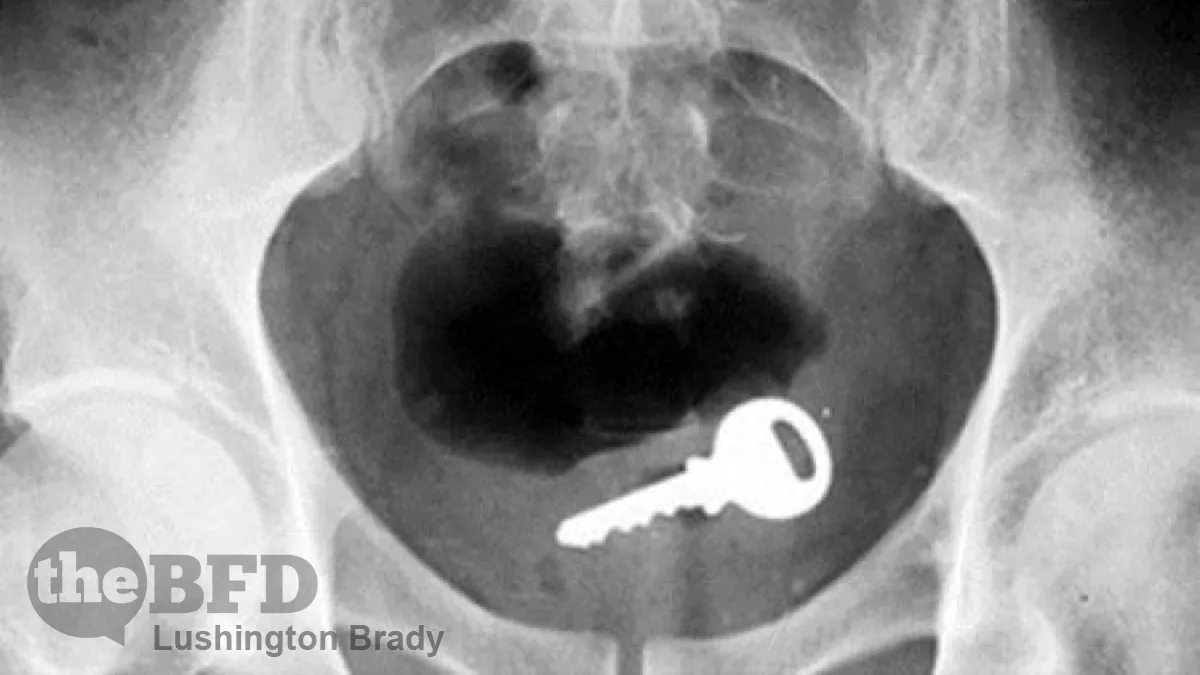

What Are Americans Putting up Their Jacksies?

There are certain traditions we all look forward to with the coming of the Festive Season: the first hot cross buns in stores, lefties whining and complaining about Australia Day, and, of course, What Did We Get Stuck In Our Rectums Last Year? For the uninitiated, this annual festive tradition